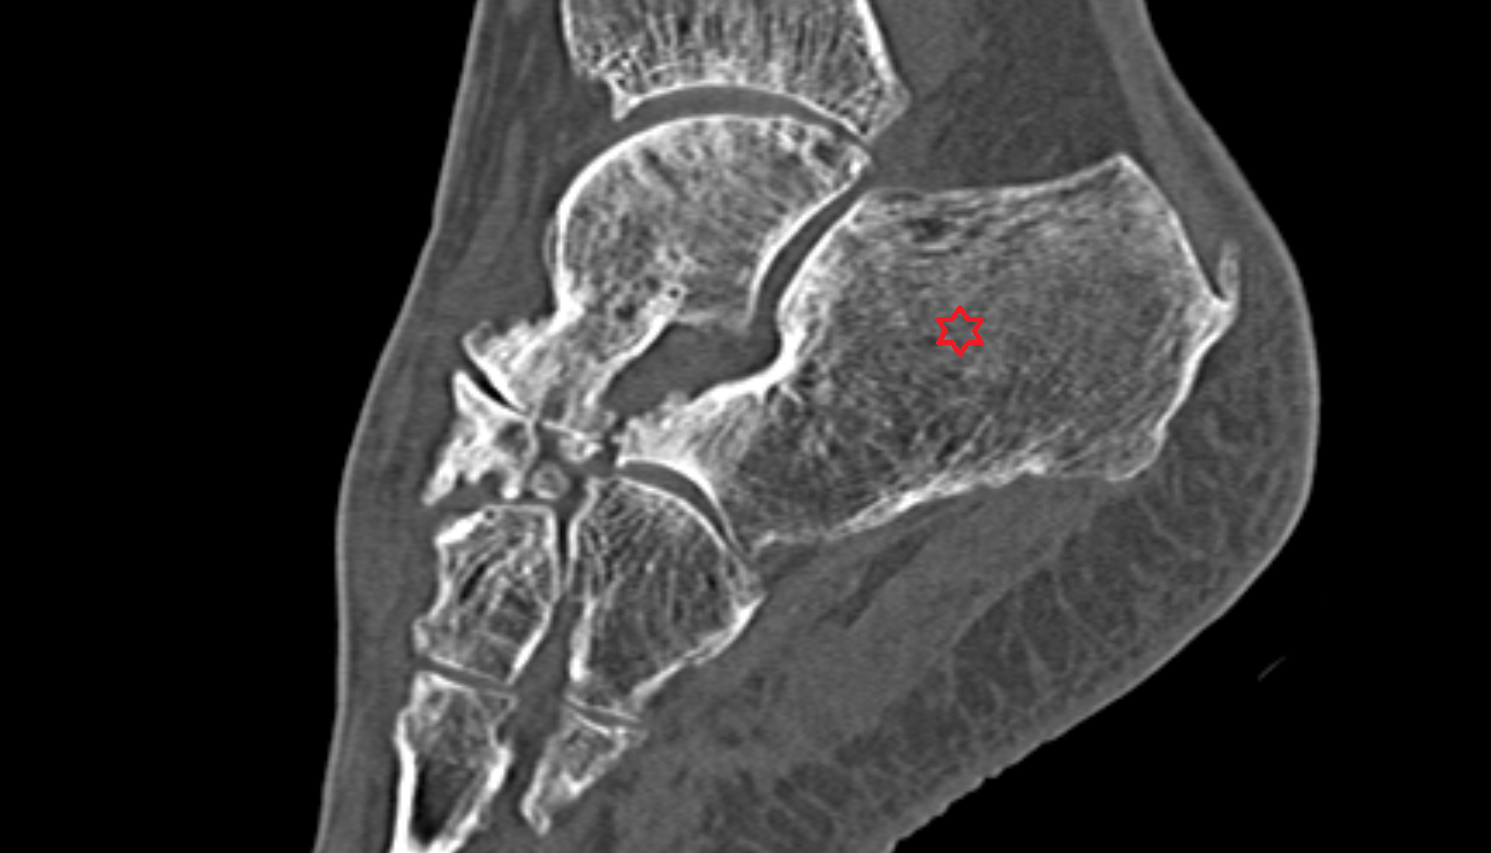

- Calcaneus